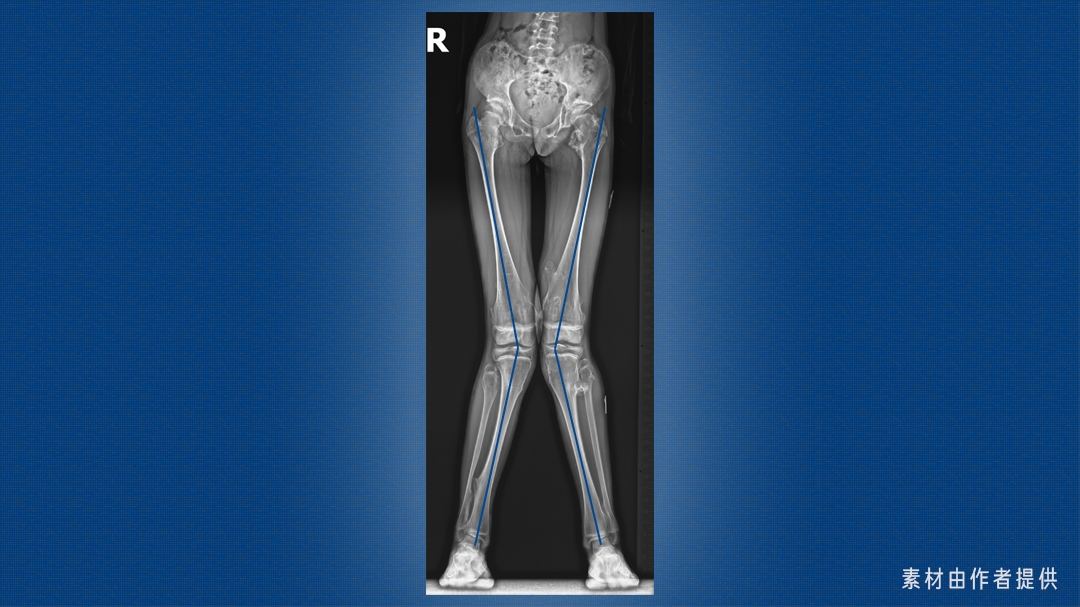

这是一双 X 型腿,医学上称为「膝外翻」,大腿和小腿轴线的交点偏向身体中轴线。

这个角度一般用胫股角来衡量,也就是大腿和小腿的轴线在膝关节处的夹角,其数值随年龄发生特征性变化。